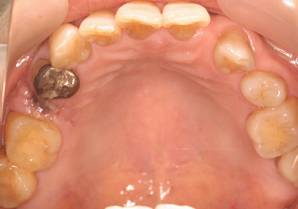

上顎

術後。上部構造はハイブリッドレジンです。しっかり嚙めるようになり喜んでいただきました。

上部構造装着後6年。ハイブリッドレジンを使用したため、少し艶がなくなってきました。上部構造の材料には金属、ハイブリッドレジン、セラミックなどがあります。セラミックはきれいですが欠けやすいため、最近はフルジルコニアを使っています。

上顎 少しすり減ってきました。